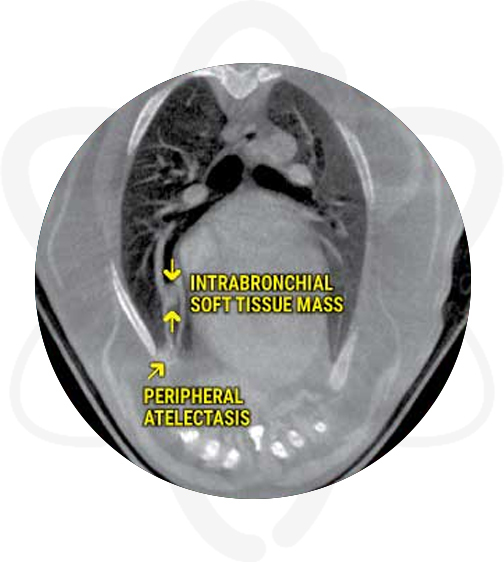

11 Year Old German Shepherd With History of Coughing

Patient is a 11 yr old, FS, German Shepherd Mix with a 4-month history of coughing that improves while she is on antibiotics.

- Intrabronchial soft tissue mass lesion right middle lung lobe with complete obstruction

- Mild resorption atelectasis of the ventral peripheral aspect of the right middle lung lobe

CT found a mass that was missed on radiographs which explain the history of the cough and made a difference in the outcome by providing valuable information for surgical planning.